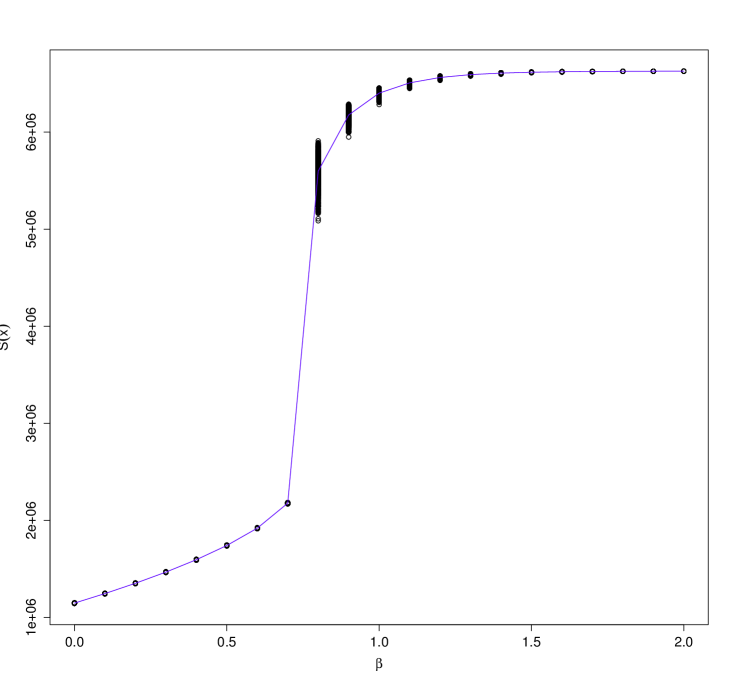

where is the number of pixels in object , are the pixels in object , and is the Euclidean distance between the coordinates of pixel and pixel . The locations of the pixels can be obtained from an exemplar image that has been manually labelled. The mean is the average spatial displacement of the object between images, while the variance represents the degree of uncertainty. Fig. 1 illustrates external field priors with increasing levels of spatial uncertainty for the ED phantom that is described in Section 4.

The amount of spatial variability in our application is quite small (standard deviation of ) relative to the size of the images (). We reran the model using external field priors with increasing levels of uncertainty ( up to , illustrated in Fig. 1) to measure the relationship between the strength of the prior and the resulting segmentation accuracy. The pixel-wise misclassification rates for the 27 cone-beam CT scans are shown in Fig. 4. We found that there was a strong relationship, with the proportion of misclassified pixels increasing sharply at first, but then gradually levelling off. As the uncertainty increases, we would expect that the misclassification rate would approach 86.8%, the accuracy that is observed without the external field prior.